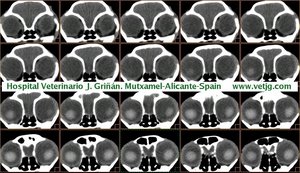

imágenes de TC en el gato | |||||||||||

Tomografía computarizada helicoidal |